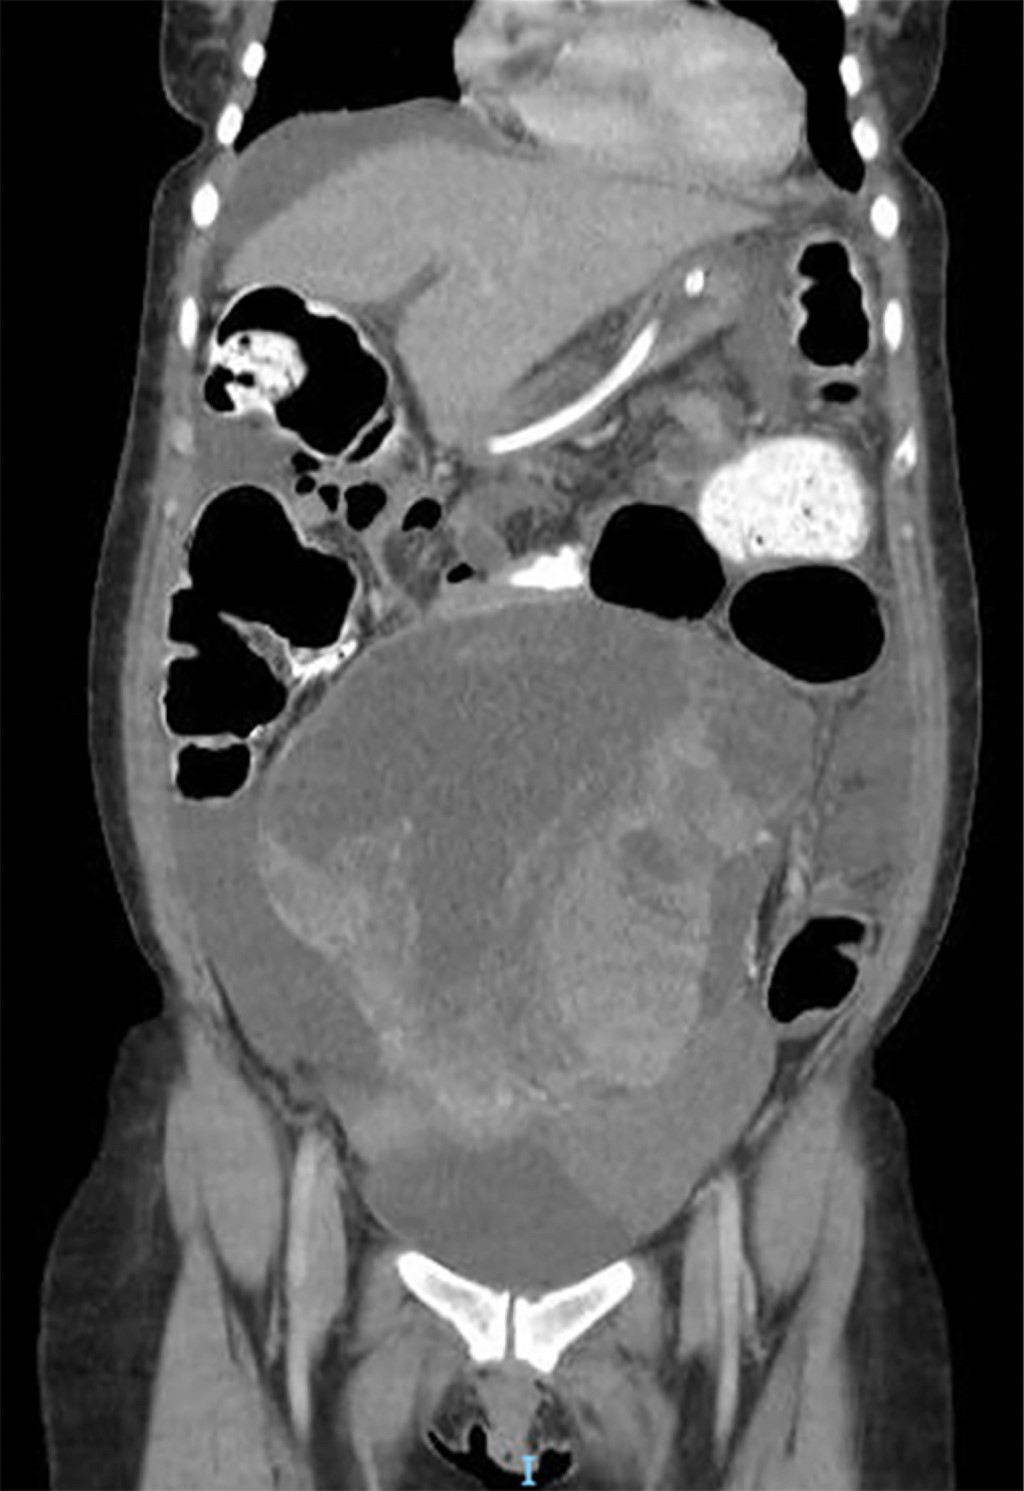

Se presenta una mujer de 51 años, con antecedentes de VIH sin adherencia al tratamiento antirretroviral, quien consultó por dolor abdominal difuso de tres meses de evolución y constipación en los últimos 10 días. En el examen físico, se evidenció abdomen distendido con falta de eliminación de gases sin signos de irritación peritoneal. Presentaba un tumor palpable en hipogastrio que se extendía hasta la región umbilical. En el laboratorio se objetivó una elevación del antígeno CA-125 (153 U/mL; valor normal hasta 35 U/mL), con el resto de las determinaciones dentro de los parámetros normales. La tomografía abdominopelviana con contraste oral y endovenoso reveló una voluminosa formación centro pélvica de 28 × 12 × 12 cm asociada a ascitis, distensión del marco colónico y progresión del contraste oral hasta colon sigmoides (Figuras 1 y 2).

Figura 1